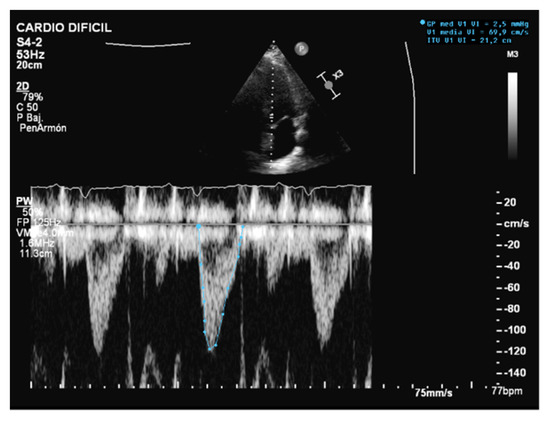

When assessing diastolic function, obtaining an E/e’ mitral ratio higher than 14.5 is associated with higher rates of weaning failure, even in atrial fibrillation [13,19,20], as are E waves higher than 0.87 m/s [13,21] (Figure 1). However, this method is less reliable in acute decompensated heart failure and left ventricles with larger volumes, where significant mitral regurgitation can lead to underestimation, as well as in resynchronization therapy and wide QRS and the subsequent change in septal e’ due to its abnormal motion [22,23].

Figure 1.

E wave height, deceleration time, and A wave. Normal filling pattern.